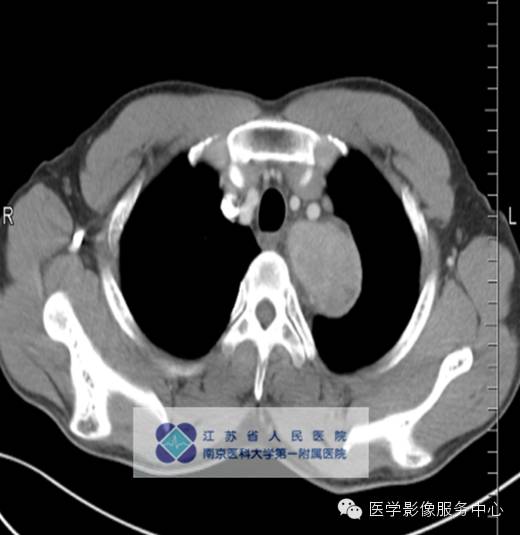

影像分析:左上、后纵隔内见类圆形软组织密度增高影,密度尚均匀,边缘清晰,增强扫描均匀强化。

门脉期病灶均匀强化,但增强值小于动脉期,仍高于周边软组织密度;

平衡期病灶持续强化,呈略高或高密度。外周有点状异常增强的小血管,可能滤泡间大量毛细血管增生,周围有滋养血管所致。